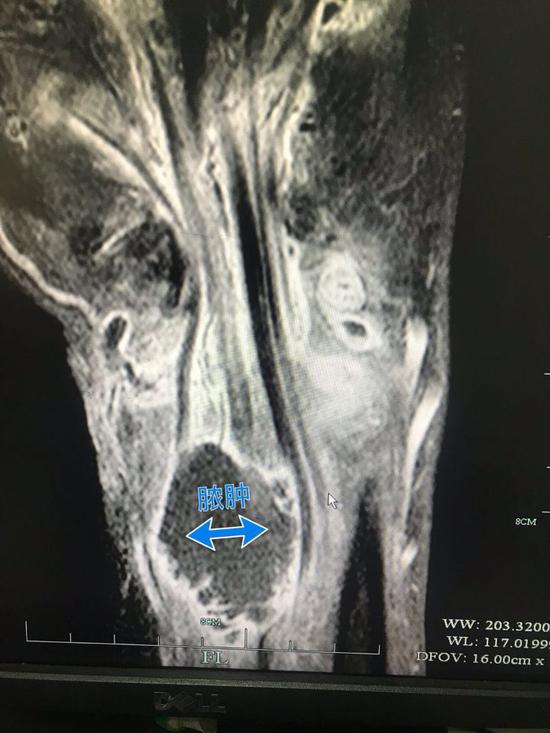

半年之后,姚先生找到了杭州的一家醫(yī)院,檢查顯示姚先生的右手腕持續(xù)流膿,伴隨著惡臭和疼痛,CT片顯示膿腫肌腱斷裂,醫(yī)生告訴姚先生,這種情況可能要截肢。